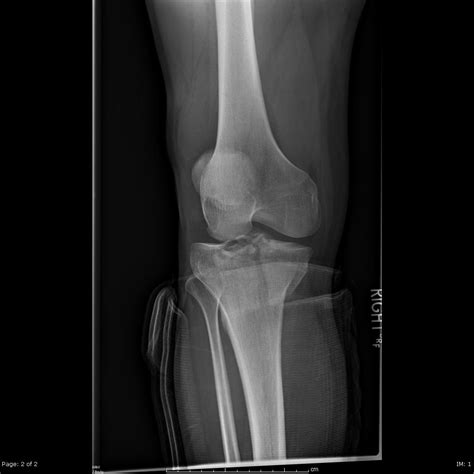

The tibia is the larger of the two bones in your lower leg, and its top surface, the tibial plateau, is divided into two sections: the lateral (outer) and the medial tibial plateau (inner). This surface is covered in articular cartilage, a smooth, tough tissue that allows the femur to glide seamlessly over the tibia during movement. The medial side is generally larger and slightly concave compared to the lateral side, which helps accommodate the curvature of the medial femoral condyle.

Because the medial side of the knee naturally bears more weight during certain phases of the gait cycle, it is a common site for degenerative changes. When this surface becomes damaged due to acute trauma or long-term wear and tear, it can lead to significant mobility issues and chronic pain.